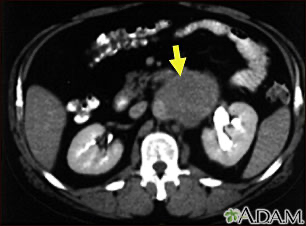

| Stadien: Ann-Arbor (I–IV) + Risikofaktoren | Wichtige Subtypen: indolent: Follikuläres Lymphom (oft „watch & wait“) aggressiv: Diffus großzelliges B-Zell-Lymphom |

Stadium IV

- Disseminierte Organbeteiligung (Leber, KM, Lunge etc.)

- unabhängig vom LK-Befall